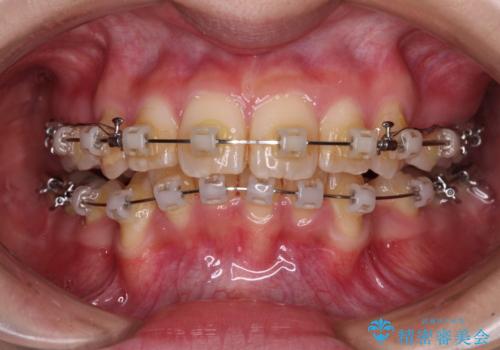

- クリアブラケット

- 2年9ヶ月

- 前方に飛び出した前歯と、下顎の八重歯を気にして来院された患者様です。

口元の突出感を改善するため、上下左右の第一小臼歯4本を抜歯し、ワイヤー装置にて矯正治療を行うこととしました。